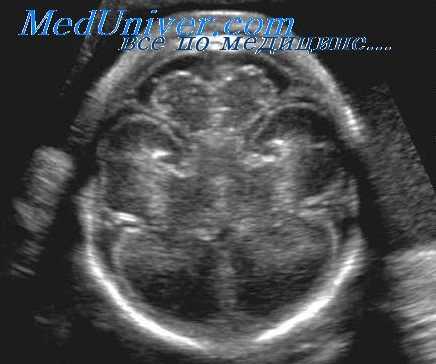

(Справа) У данного плода с Т21 и заметным увеличением ТВП и дефектом предсердно-желудочковой перегородки была диагностирована незначительная вентрикуломегалия. Измерение (калипер) проводилось на уровне атриума желудочка, в месте начала дорсальной части сосудистого сплетения (клубочка). (Слева) У данного плода с дисгенезией мозолистого тела и отсутствием ППП желудочек имеет форму слезы и расширен кзади, а передние рога смещены вбок и параллельны серпу большого мозга. Подобную морфологию боковых желудочков также называют кольпоцефалией.

(Справа) При МРТ на Т2-ВИ в аксиальной и фронтальной плоскостях у другого плода визуализируются кольпоцефалия смещенный кверху III желудочек и параллельные друг другу передние рога. Во фронтальной плоскости видны передние рога в форме трезубца. (Слева) При ТВУЗИ в аксиальной плоскости у плода на 20-й неделе гестации видна двусторонняя вентрикуломегалия. Плод мужского пола. У его сиблинга наблюдался Х-сцепленный ССВ.